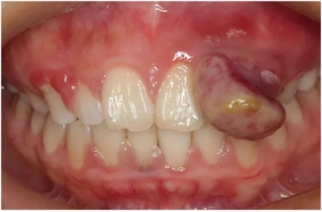

2.牙龈瘤:有些孕妇还会发现牙龈上长出了红红的鼓包(如下图),我们称之为妊娠性龈瘤,在分娩后一般会自行缩小,若仍不消退可以进行手术。

妊娠期牙龈瘤